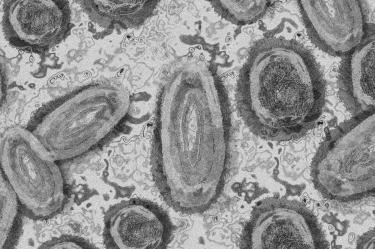

Confirma Coahuila primer caso de viruela del mono

La Secretaría de Salud de Coahuila, confirmó el primer caso de viruela del mono, en una persona originaria del Estado de México.

La Secretaría de Salud de Coahuila, confirmó el primer caso de viruela del mono, en una persona originaria del Estado de México, quien se encuentra en Saltillo, por diversas actividades.